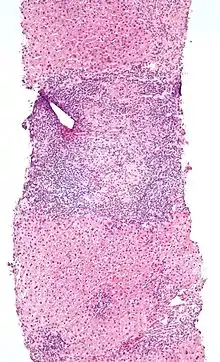

Low-magnification micrograph of PBC, H&E stain

On microscopic examination of liver biopsy specimens, PBC is characterized by chronic, nonsuppurative inflammation, which surrounds and destroys interlobular and septal bile ducts. These histopathologic findings in primary biliary cholangitis include:[31]

The Ludwig and Scheuer scoring systems have historically been used to stratify four stages of PBC, with stage 4 indicating the presence of cirrhosis. In the new system of Nakanuma, the stage of disease is based on fibrosis, bile duct loss, and features of cholestasis, i.e. deposition of orcein-positive granules, whereas the grade of necroinflammatory activity is based on cholangitis and interface hepatitis. The accumulation of orcein-positive granules occurs evenly across the PBC liver, which means that staging using the Nakanuma system is more reliable regarding sampling variability.

Histopathology stages (by Ludwig and Scheuer systems)

- Stage 1 – portal stage: Normal-sized triads, portal inflammation, subtle bile duct damage: Granulomas are often detected in this stage.

- Stage 2 – periportal stage: Enlarged triads, periportal fibrosis and/or inflammation, typically characterized by the finding of a proliferation of small bile ducts

- Stage 3 – septal stage: Active and/or passive fibrous septa

- Stage 4 – biliary cirrhosis: Nodules present, garland or jigsaw puzzle pattern